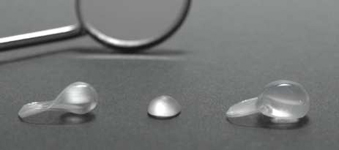

Osmotický hydrogelový expander měkkých tkání

Velmi často je pro zavedení implantátu vzhledem k nedostatku kosti provést její doplnění tzv. augmentaci. Naše zařízení je zaměřené na doplnění nedostatečného množství kosti a používá celou řadu moderních postupů metod a matriálů. Velký význam pro úspěšné doplnění kosti hraje i dostatečné množství měkkých tkání – sliznice, která musí dodané množství kosti dokonale překrýt a nesmí ani tlakem způsobit jeho resorpci. Jednou z nejmodernějších a velice šetrnou metodou pro získání dostatečného množství měkkých tkání je použití osmotického hydrogelového expanderu.